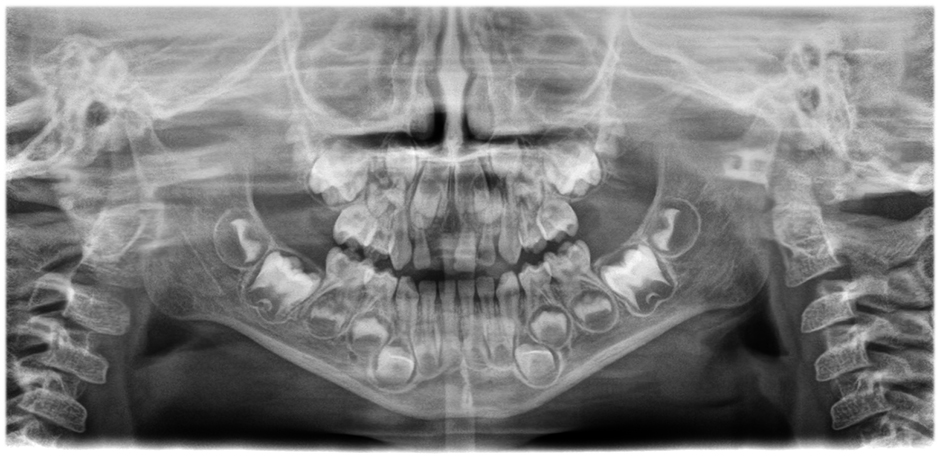

• Olağanüstü netlik ve çözünürlükte panorama görüntüler,

Hasta konumlandırma düzeltmesi ile sorunsuz bir şekilde entegre edilmiş yenilikçi 21 katmanlı otomatik odaklama sistemi.

Farkı görmek için kaydırıcıyı hareket ettirin (sol görüntü otomatik odaklama ve hasta konumlandırma düzeltmesi olmadan, sağ görüntü otomatik odaklama ve hasta konumlandırma düzeltmesi ile).